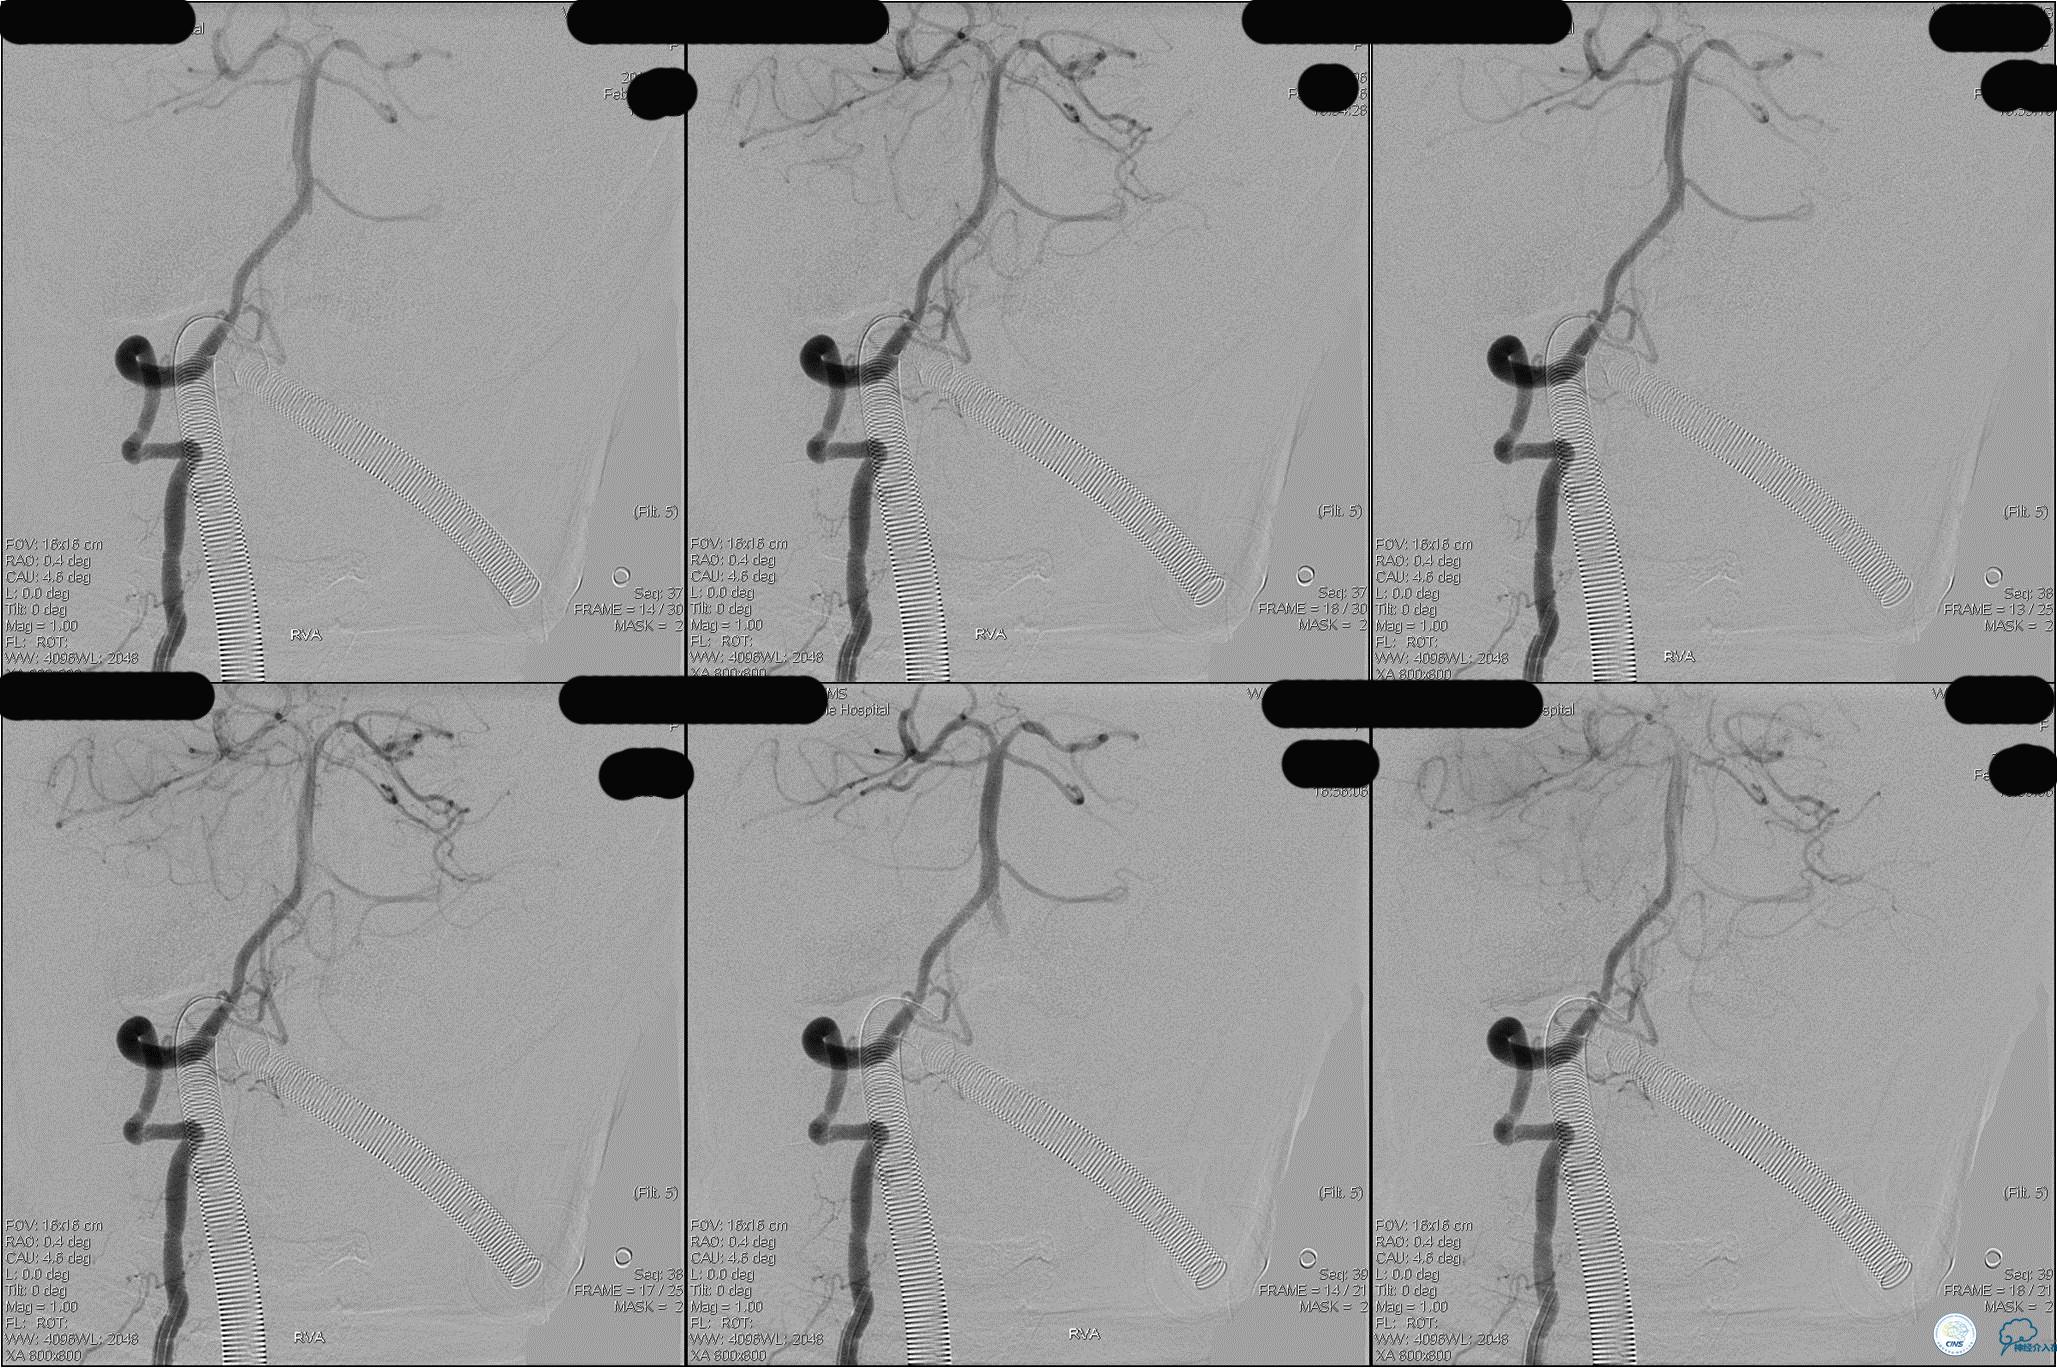

第3次取出血栓

》DSA资料(第3次取栓后,发病10h)

》DSA资料(视察30min后,左椎造影)